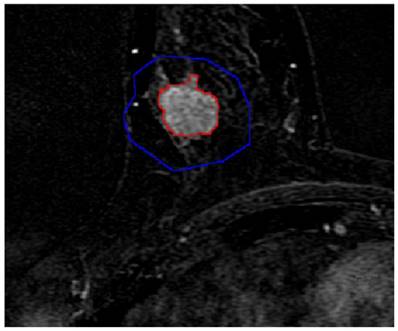

First, a randomly selected subject (aged 43 years) was used to illustrate the results obtained with the manual method (Fig. 1), as well as the semi-automatic segmentation of lesions (Fig. 2) and the quantitative analysis (Fig. 3).

Figure 2

Semi-automatic segmentation result of the breast lesion based on the proposed method for the randomly selected case (the colors were set to red for the lesion margin and blue for the ROI margin). In order to facilitate the observation, this image partially enlarged.